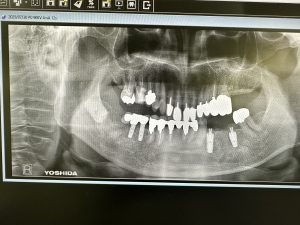

今日は2件インプラントブリッジセット

ほぼ2か月で終了

上下問わず、オペ時、計測値が良い場合は6w後再計測し著しい下降なくI SQ70以上であれば印象しています

画像からも歯肉緣からプラットフォームまでの4ミリルールが守られており良い絵面だ🤪